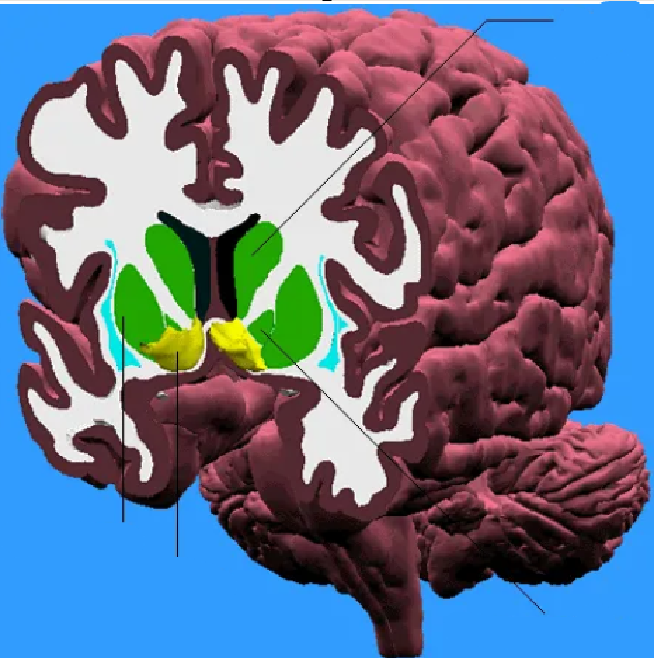

Thalamus (pink) and hypothalamus (yellow): their medial surfaces border the third ventricle (blue).

Overlaying the green cingulate and parahippocampal gyri with the purple hippocampus highlights the limbic lobe. Yellow = fornix. Brownish pink = hypothalamus

The purple hippocampus is visualized tracing the ventricular system (turquoise).